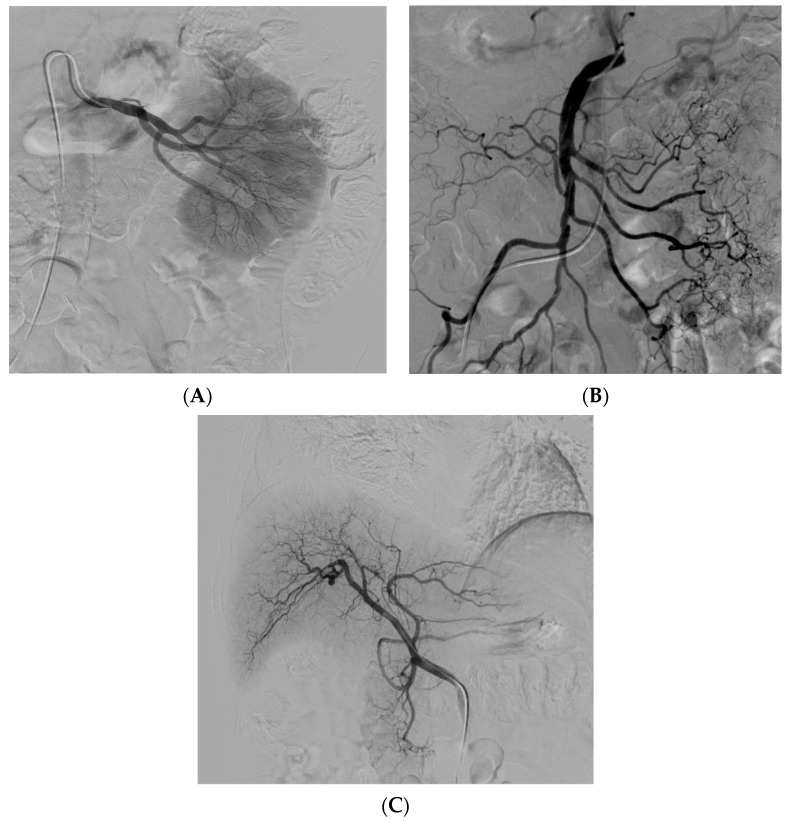

經動脈干細胞注射(TASI)可能被認為是一種理想的選擇性遞送方法,在所需器官中具有最佳分布和高干細胞濃度。在組織取樣和干細胞分離處理(自體或異體)之后,該過程基本上包括通過動脈通路(最常見的是股動脈)引入導管。然后,在熒光鏡和造影劑引導下,將導管放置在所需的供血動脈(肝動脈、腸系膜動脈或腎動脈)中,以進行隨后的干細胞注射。圖2)。

圖2:腎 (?A?)、腸系膜上動脈 (?B?) 和肝動脈 (?C?) 的血管造影插管

圖2

導管定位確保對所需組織進行選擇性治療,避免非目標干細胞輸注。